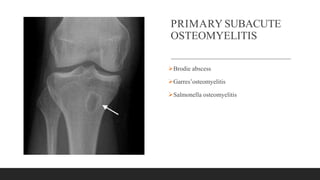

PRIMARY SUBACUTE

OSTEOMYELITIS

Brodie abscess

Garres’osteomyelitis

Salmonella osteomyelitis

On plain roentgenograms a Brodie abscess

generally appears as a lytic lesion with a rim of

sclerotic bone but can have a markedly varied

appearance.